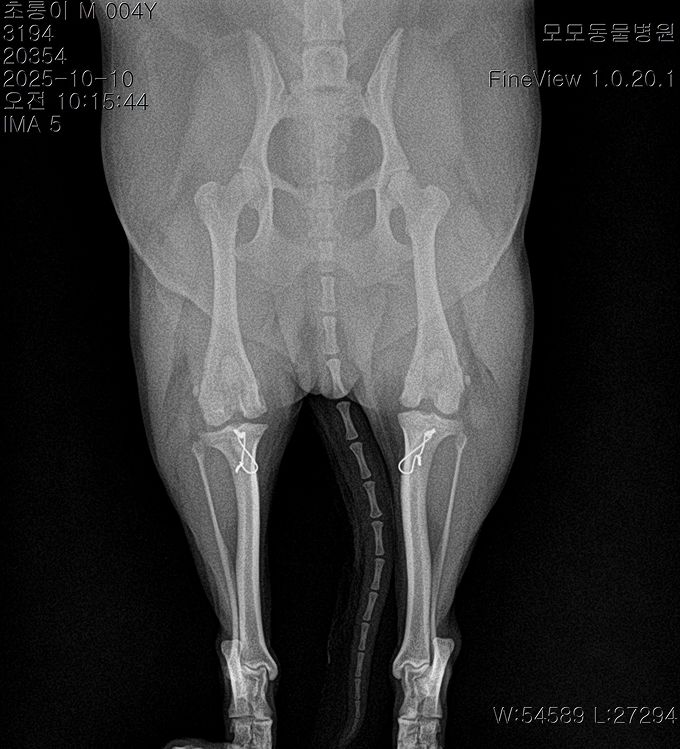

BEFORE

AFTER